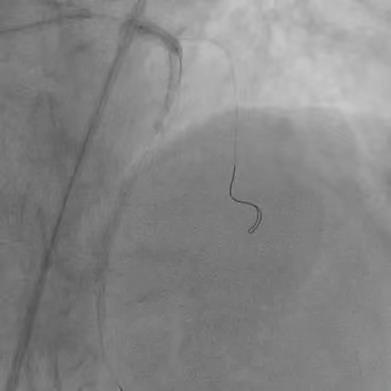

IABP植入后,旋磨导丝顺利经左主干通过病变置于LAD远段,先后使用1.5mm、1.75mm磨头旋磨,而后,在分支均保护的情况下,植入3.0*24mm支架,并选择3.5*12mm NC 30atm行后扩。![]() 先后1.5mm、1.75mm磨头旋磨 ![]() 分支均保护的情况下,3.0*24mm支架植入 然而,虽经NC球囊反复后扩张,左主干支架依然膨胀不良,考虑为钙化厚度过大所致。此时,再行球囊扩张无效、再行旋磨磨头直径不够;为求进一步管腔获得,果断启动Shockwave IVL。为保证IVL球囊与支架及深层钙化紧密贴靠,选取3.5*12mm Shockwave IVL球囊,通过病变后,迅速充盈电解液并扩张至4atm,触发血管内冲击波,每周期10个脉冲、耗时10秒,共行6个周期IVL治疗,之后将脉冲球囊扩张至6atm。复查造影及IVUS,主干最小管腔面积从4.9mm2上升为7.3mm2。随即又在前降支的中远段重度狭窄处顺利植入了2.5*18mm的支架。患者于三天后顺利出院,胸闷症状明显改善,活动耐量显著增加。 ![]() ![]() ![]() 3.5*12mm Shockwave IVL左主干支架内处理前后对比 术者总结